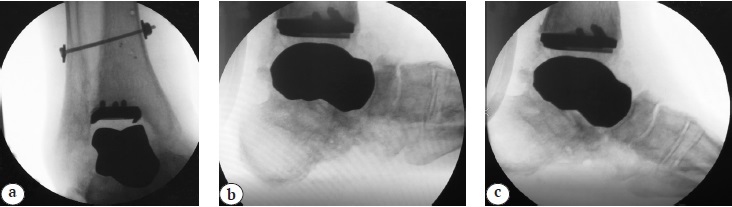

The edema maintained of the operated lower limb for 3 months after surgery, significantly decreasing overnight. The control radiography showed no signs of instability, maintaining a good anatomical position of the talus implant and the tibial component of the ankle endoprosthesis. The total volume of passive and active movements in the ankle joint at the time of the last control examination is 28°, of which the back flexion is 12° plantar flexion is 16°, which can be characterized as an acceptable result compared to the normal range of motion in the joint (Fig. 7, 8).

Fig. 7. Control X-rays of the ankle joint 20 months after surgery: a — AP plane, good position of hardware is noted, preservation of the ankle contours; b, c — functional X-rays in the lateral plane of the plantar and dorsal flexion: good position of the endoprosthesis components is noted, total ROM is 28°